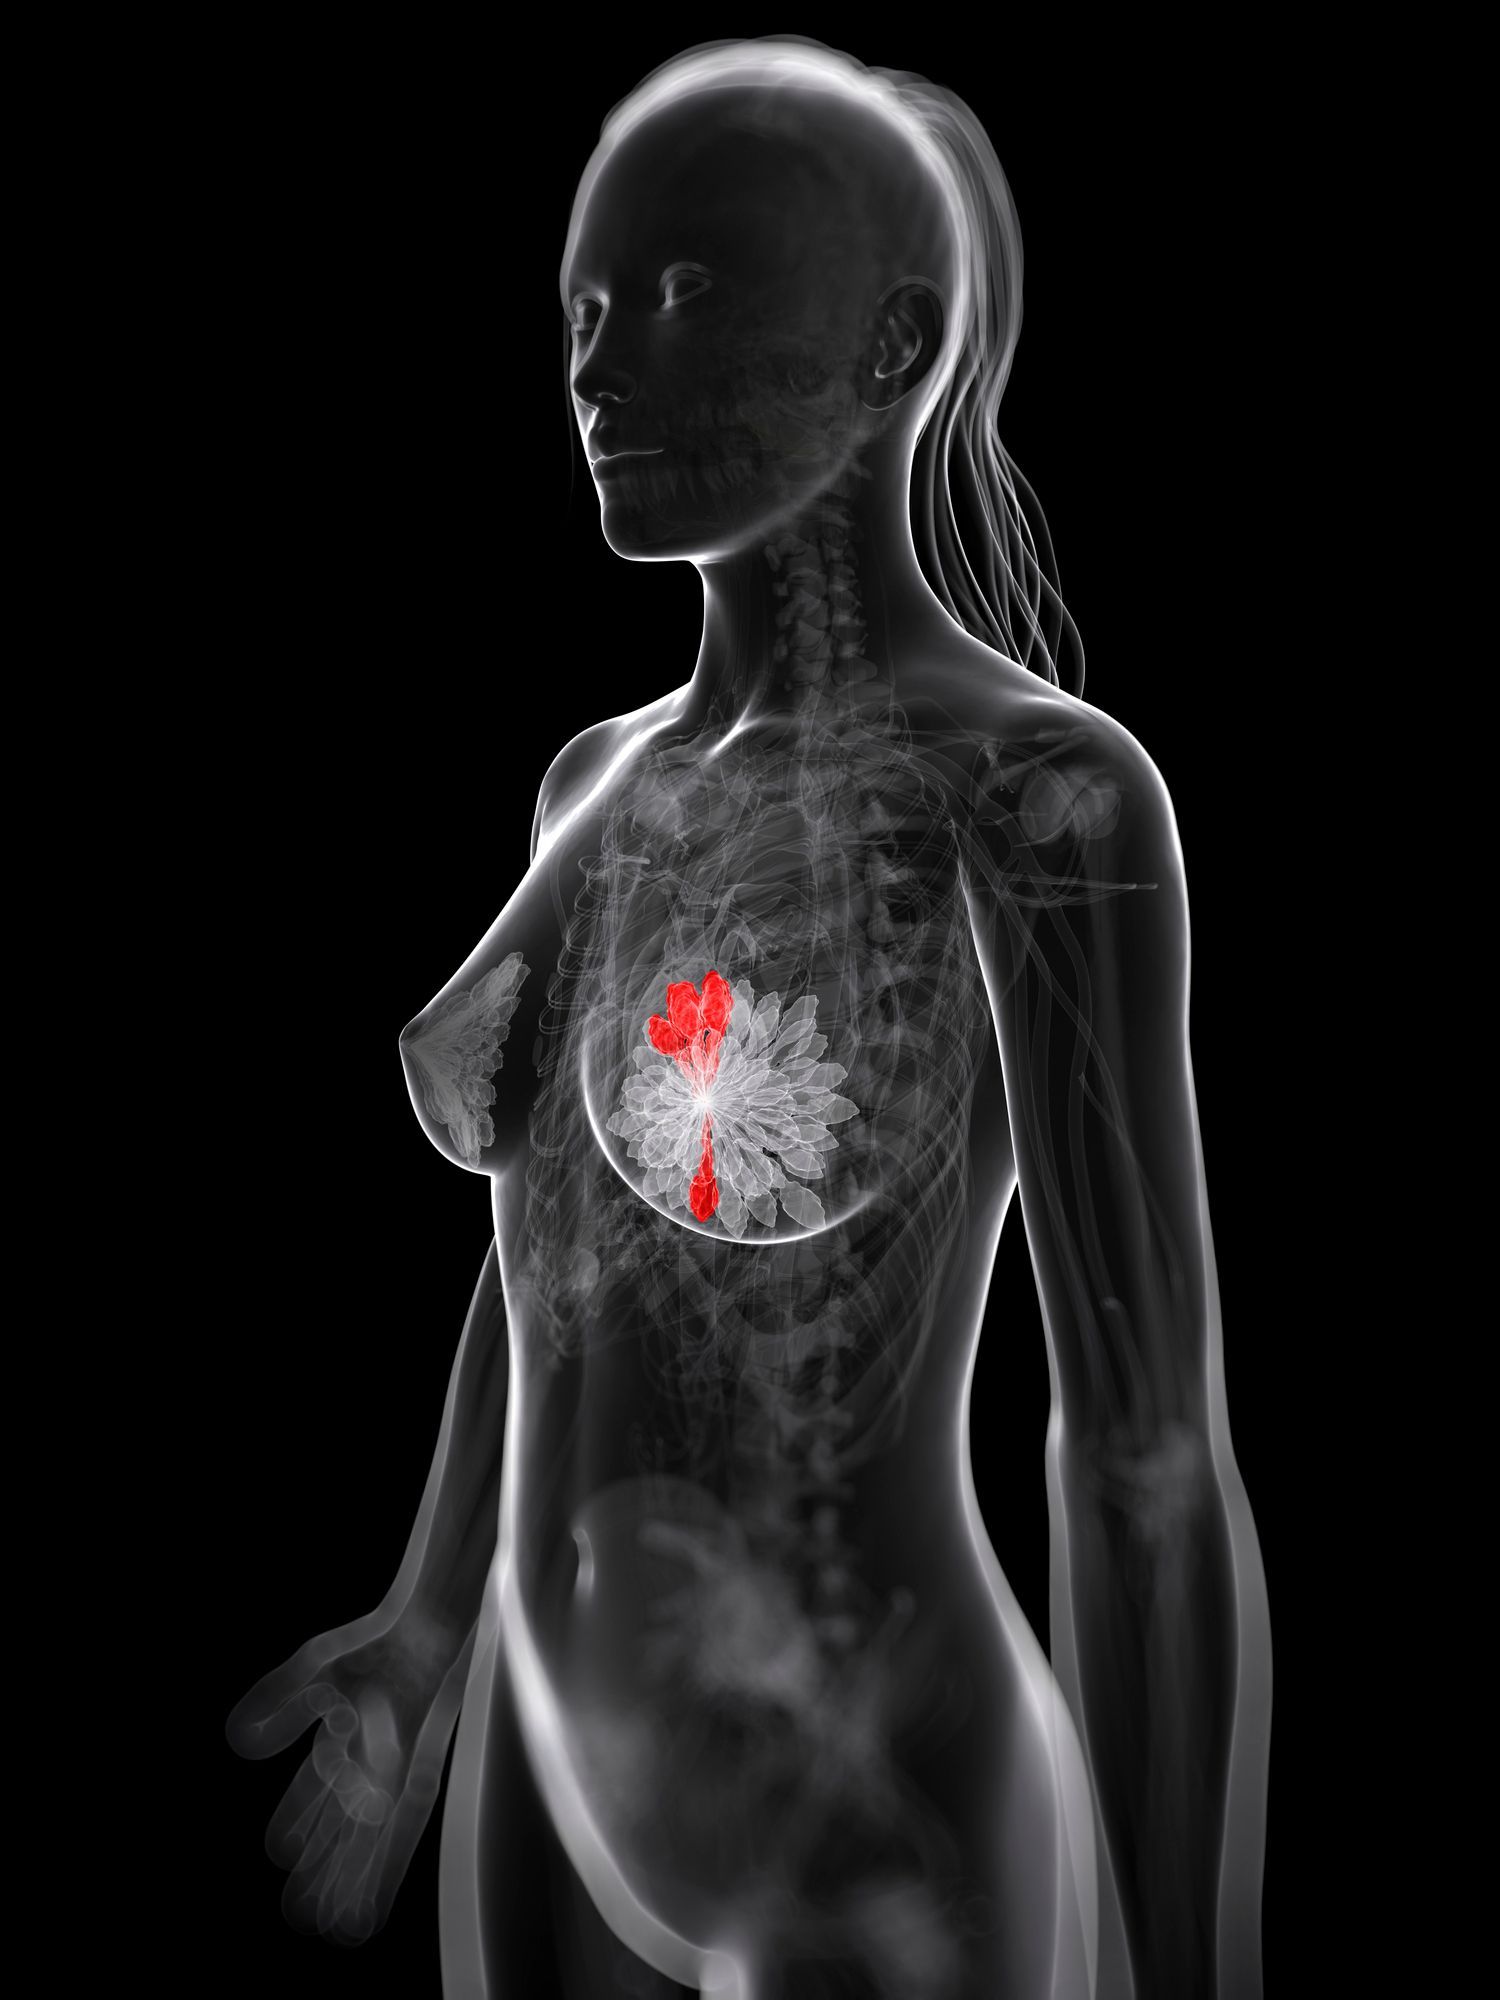

Tomosintesi 3D, una tecnica disponibile presso il nostro centro di

Catania che permette di acquisire immagini della mammella a strati sottili. Questo elimina il problema della sovrapposizione dei tessuti, migliorando significativamente l'individuazione di piccole lesioni, specialmente in seni densi, e riducendo il numero di falsi positivi. Utilizzare la

Opzioni diagnostiche avanzate per la tutela della salute femminile.

Servizi Diagnostici Integrati a Catania è interamente dedicata alla tutela della salute femminile, fornendo strumenti essenziali per lo screening e la diagnosi precoce. Offriamo sia la

Mammografia Digitale che l'Ecografia Mammaria, due metodiche che, singolarmente o in combinazione, costituiscono il pilastro della diagnostica senologica. La scelta tra i due esami o la loro integrazione dipende da specifici fattori clinici, come l'età della paziente e la densità del tessuto mammario, e viene stabilita in accordo con il medico curante. Il nostro obiettivo primario è fornire un servizio di